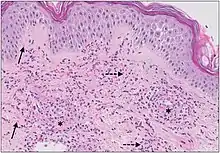

Example of hypersensitivity vasculitis | |

The small vessels in the skin affected are located in the superficial dermis and include arterioles (small arteries carrying blood to capillaries), capillaries, and venules (small veins receiving blood from capillaries).[5] In general, immune complexes deposit in vessel walls leading to activation of the complement system. C3a and C5a, proteins produced from the complement system, attract neutrophils to the vessels.[9] Once activated, neutrophils then release preformed substances, including enzymes causing damage to vessel tissue.[9] Evidence of this process can be seen with a sample of removed skin tissue, or biopsy, viewed under a microscope. Neutrophils are seen surrounding blood vessels and their debris within vessel walls, causing fibrinoid necrosis. This finding on histological examination is termed "leukocytoclastic vasculitis".[5]